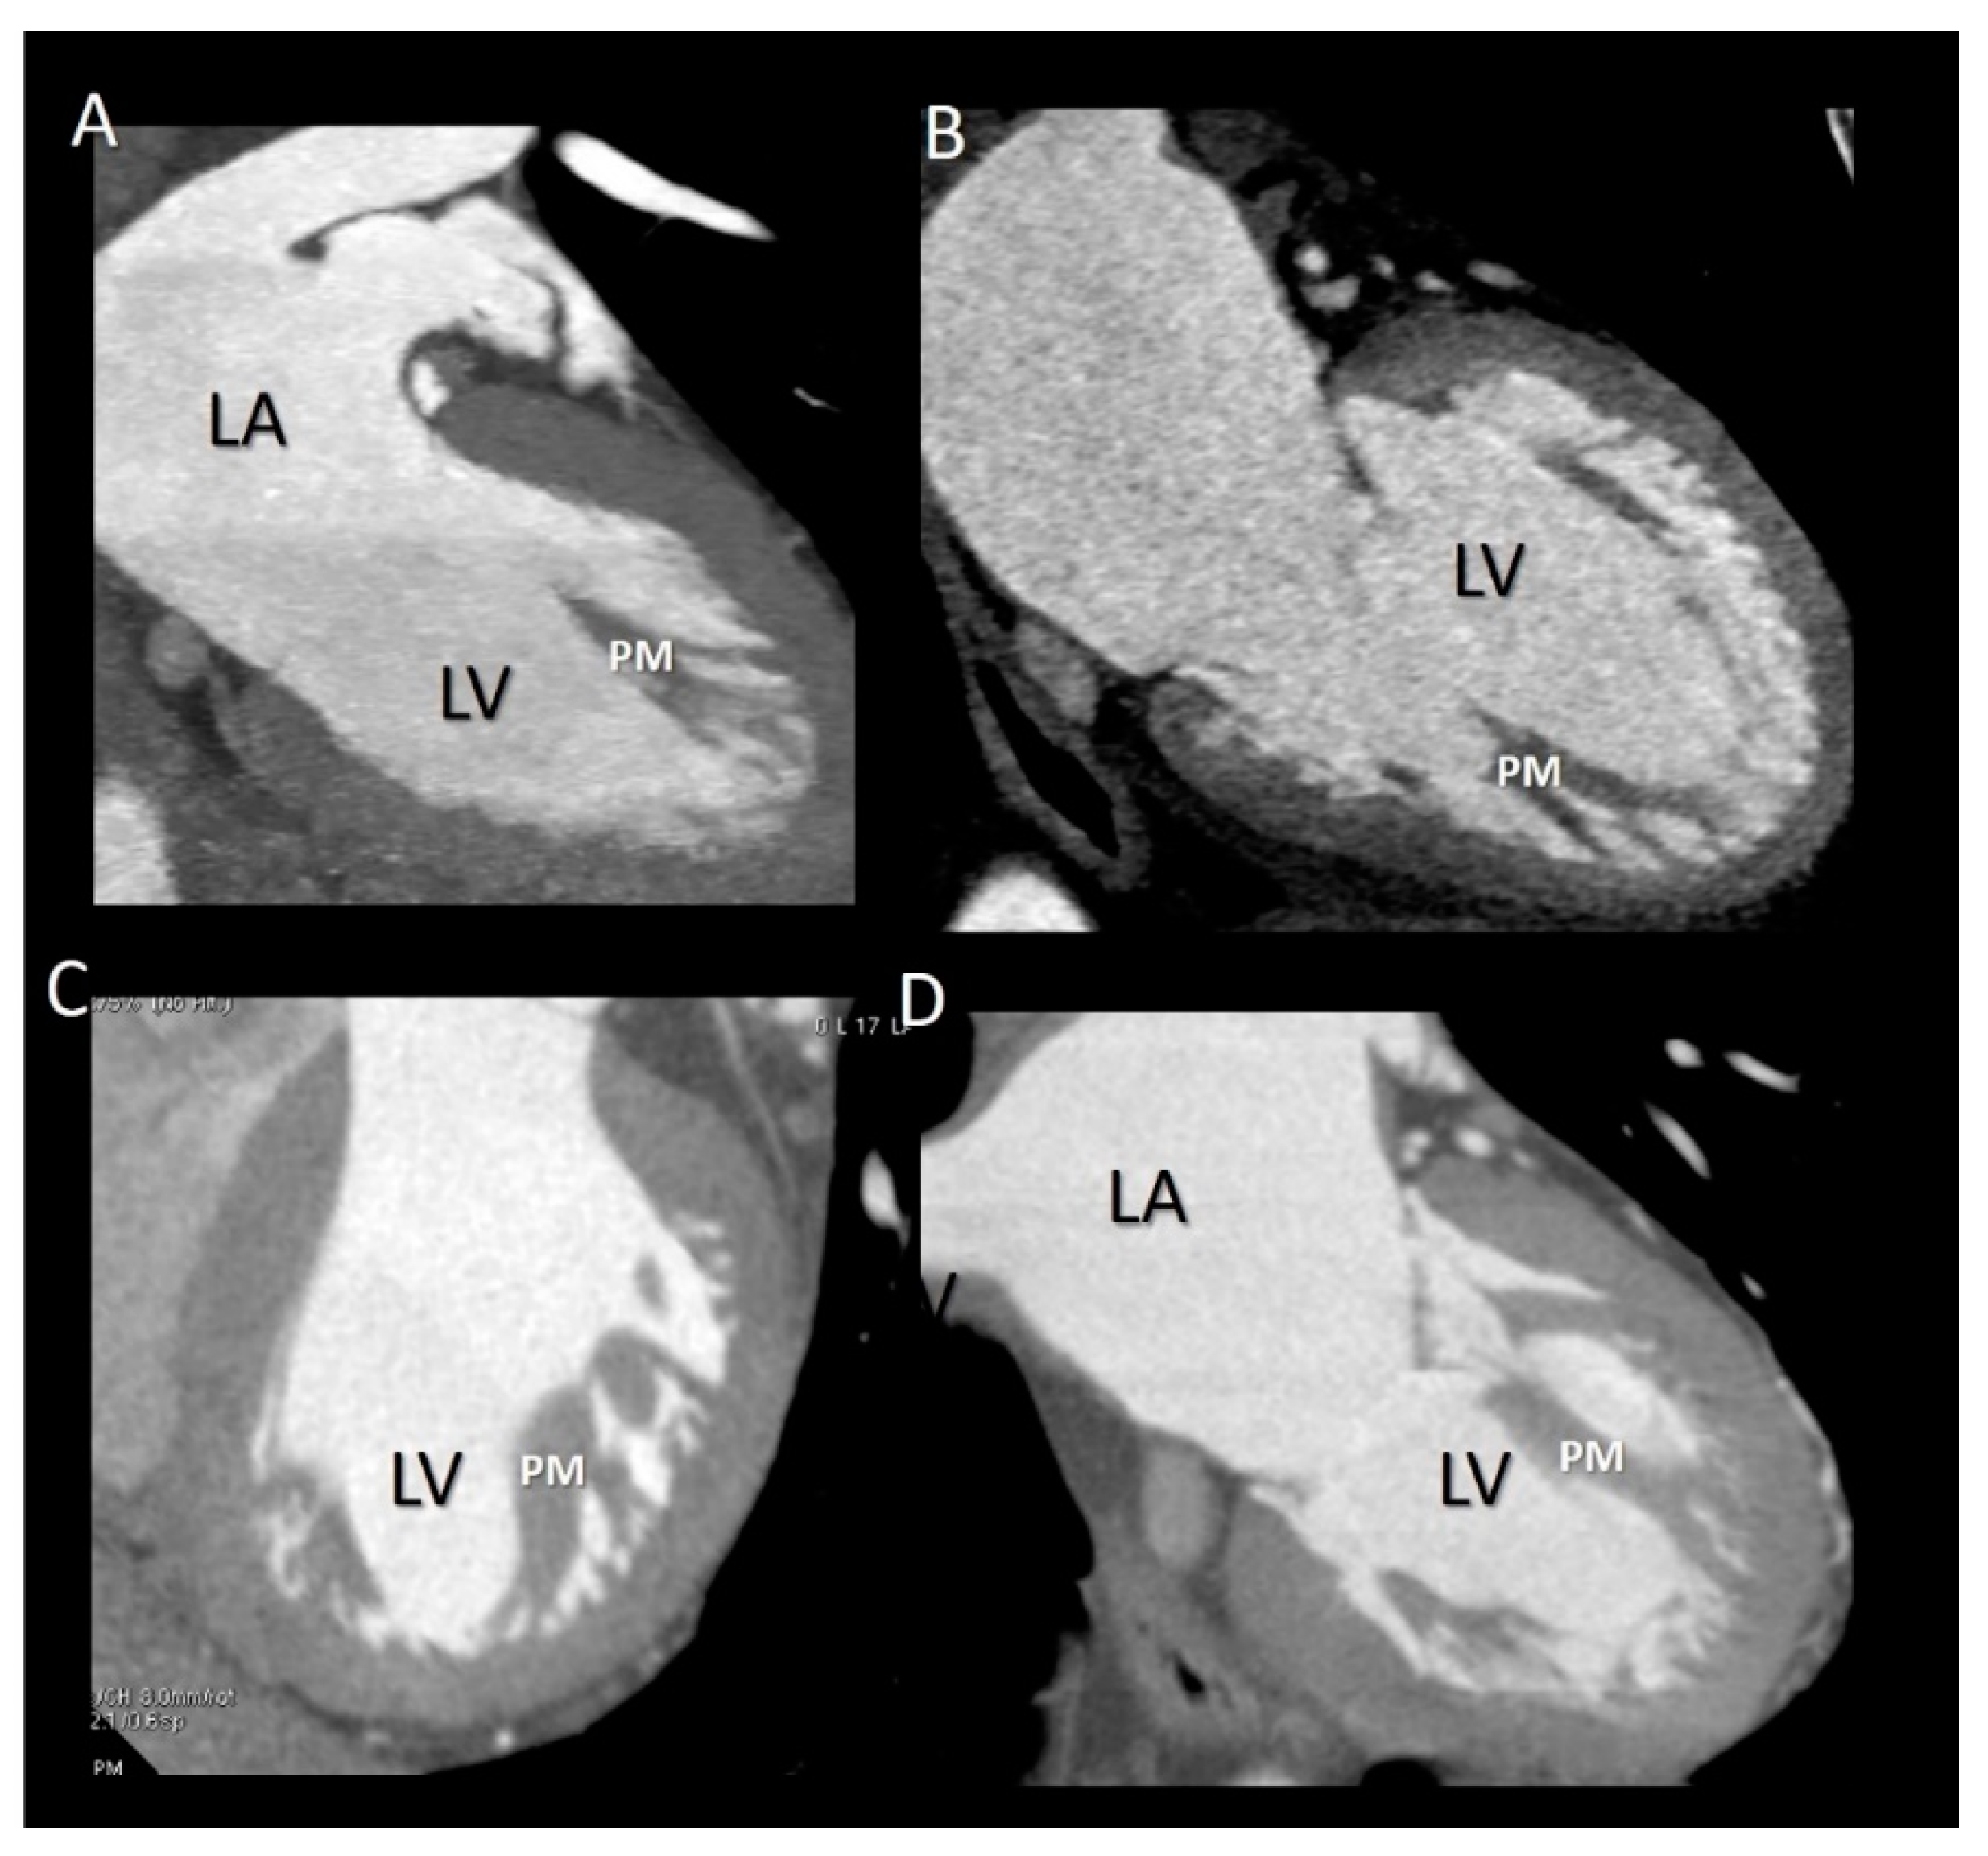

The papillary muscles (PMs) originate from the apical third of the left ventricle and are usually organized into two groups, the anterior-lateral and the posterior-medial sited below the corresponding commissures. As for the chordal apparatus, considerable variation in size, length and configuration (single PM with or without multiple heads or multiple PMs) may occur among individuals [26,27]. However, generally, the anterior-lateral is larger than the posterior-medial PM. The long axis of PMs is parallel to the long axis of left ventricle. Each of the two groups of PMs gives rise to dozens of main chordae tendineae that insert into the medial and lateral halves of both leaflets. PMs have an essential role in the closure of the mitral leaflets. When the left ventricle contracts and shortens, the simultaneous contraction of PM maintains, at constant, the distance between the tips of the PMs and the leaflets, preventing leaflet eversion during the systole. The anterior-lateral PM has a dual blood supply from both the anterior descending and the circumflex coronary arteries while the posterior-medial PM is only dependent on the coronary artery that gives origin to the posterior descending coronary. This “asymmetric” vascularization may explain different clinical scenarios. A myocardial infarction involving the posterior myocardial wall usually results in a necrosis of the posterior-medial PM (with consequent mitral regurgitation), while an anterior myocardial infarction may affect the anterior-lateral PM. Several textbooks describe PMs as arising directly from the compact myocardium layer. Recently, this belief was challenged by CT scan imaging, which revealed that PMs arise from a network of trabeculations rather than from a single pillar [28]. The attachment on a broad mesh-like architecture could protect PMs from ventricular pressure more effectively than a pillar-like attachment. Furthermore, multiple origins allow PMs to draw blood supply from numerous pathways, thus assuring a diffuse collateral perfusion.

Imaging Techniques

All the three imaging modalities may beautifully illustrate PMs. Two-dimensional TTE/TEE and CMR, because of their high frame rate, may assess the shortening of the PM (Figure 8). Conversely, the high spatial resolution of CT allows for the obtaining of exceptional images of the variable anatomy of the PMs attachment on ventricular myocardium (Figure 9).

Figure 9.

(A–D) CT representative images showing as the base of PMs do not attach to the compact myocardium but rather to a network of trabeculations.